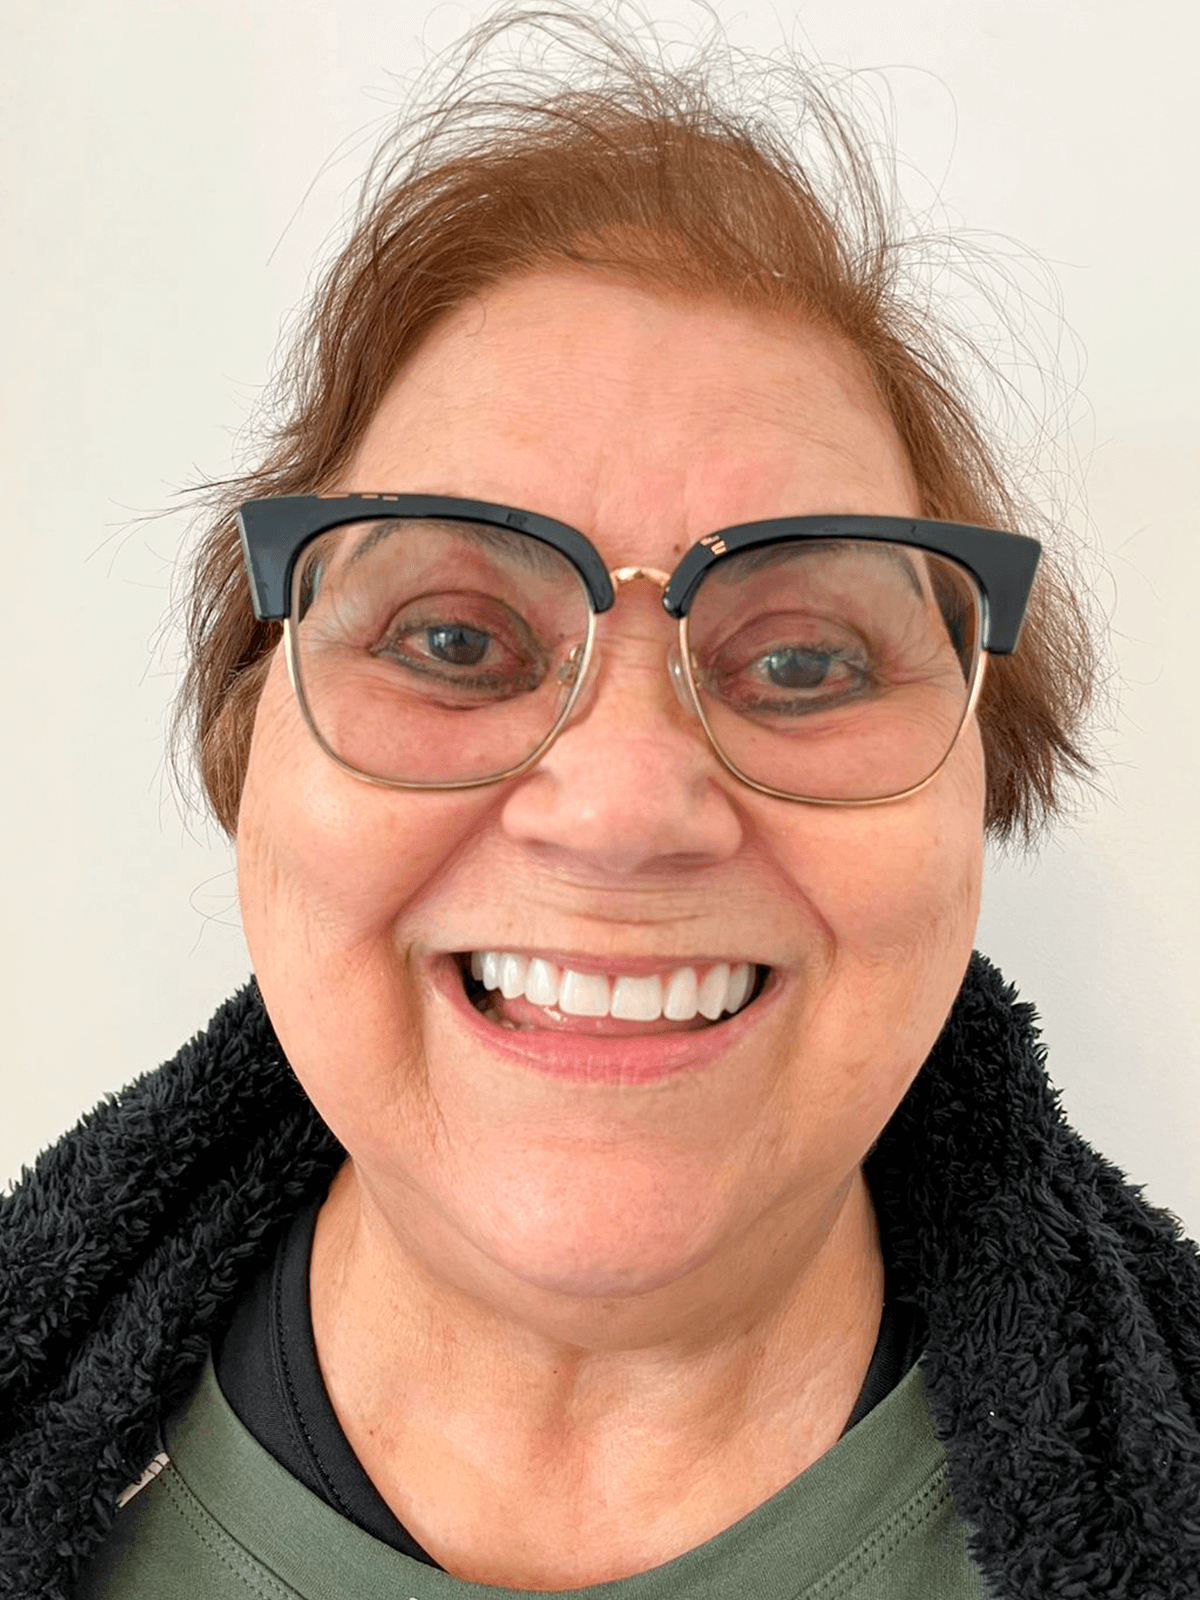

Próteses dentais

O caminho para um sorriso completo e confiante, restaurando sua estética e funcionalidade.

Implante Dentário

A solução permanente e natural para recuperar seus dentes perdidos e sorrir sem preocupações.